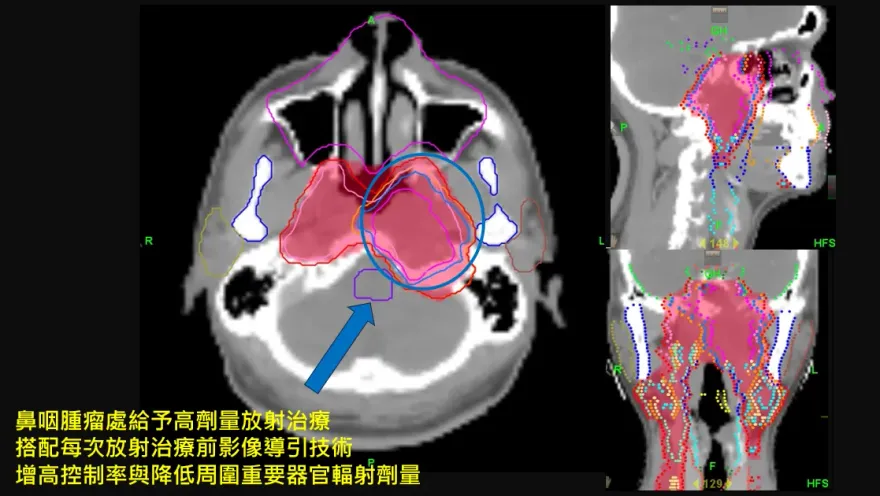

鼻咽癌

影像導引放射治療

鼻咽部腫瘤